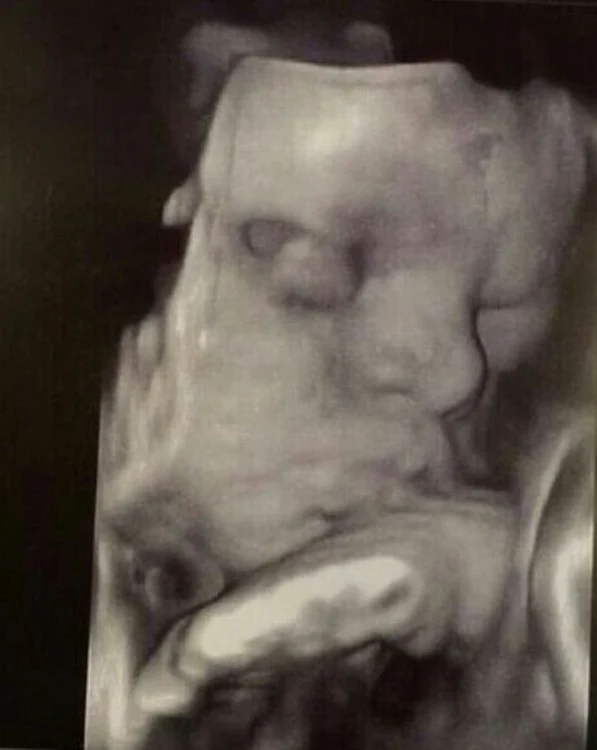

EXCLUSIV Prima poză cu bebeluşul Roxanei Vaşniuc! Prezentatoarea a izbucnit în lacrimi când a văzut-o pe fetiţa ei

Roxana Vaşniuc (30 de ani) abia aşteaptă să devină mamă şi nu mai are mult până îşi va cunoaşte bebeluşul. Prezentatoarea a dus pe picioare sarcina şi nu s-a plâns că ar avea vreo problemă. Totuşi, în urmă cu două săptămâni, blonda a ajuns la spital, fiind în pericol să nască înainte de termen. A stat internată câteva zile, timp în care medicii i-au pus perfuzii pentru a-i calma durerile şi contracţiile. A scăpat de perioada critică, iar acum se simte bine, dar continuă să ia tratament. La ultima ecografie, emoţiile au cuprins-o atât de puternic, încât a izbucnit în lacrimi când şi-a văzut bebeluşul pe ecranul unui monitor.

"Gândul că mai e puţin până o ţin în braţe e copleşitor. Trăiesc un amalgam de emoţii, de nerăbdare. Sper ca bunul Dumnezeu să-mi dea putere şi înţelepciune să fiu o mamă bună. Nu-mi dau seama cu cine seamănă, noi oricum o iubim. Mi-am făcut bagajul pentru spital, pentru că micuţa noastră este cam grăbită. Doctorul care îmi supraveghează sarcina mi-a spus să nu fac efort ca să amân cât mai mult momentul naşterii. Mai sunt cam cinci săptămâni, în mod normal până la termen. Încerc să stau cât mai mult în pat, pentru că este important ca fetiţa noastră să mai ia în greutate înainte să vadă lumina zilei", ne-a povestit Roxana Vaşniuc.